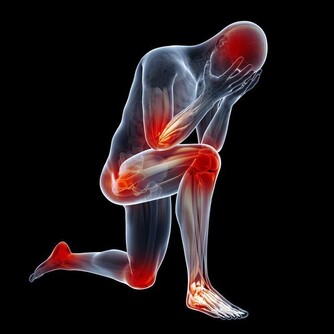

6. 運動時疼痛

如果輕輕一動就會感覺疼,那就是血栓的另一個早期預警信號。一個人從正常行為如彎腰、笑或咳嗽中感到不適,表明血栓有可能到達肺部,必須迅速治療。情況嚴重時,還要掛急診。7.原因不明的咳嗽

8. 經常腿抽筋

每個人都會時不時抽筋,但你要知道,與凝血有關的脫水也能導致肌肉痙攣。所以,如果小腿抽筋變得頻繁,這是一個嚴重的跡象,表明可能存在血栓。通常,緩解痙攣的方法是向後彎曲足部以拉伸肌肉。如果這種做法沒有幫助,並且疼痛增加,原因很可能就是血栓。